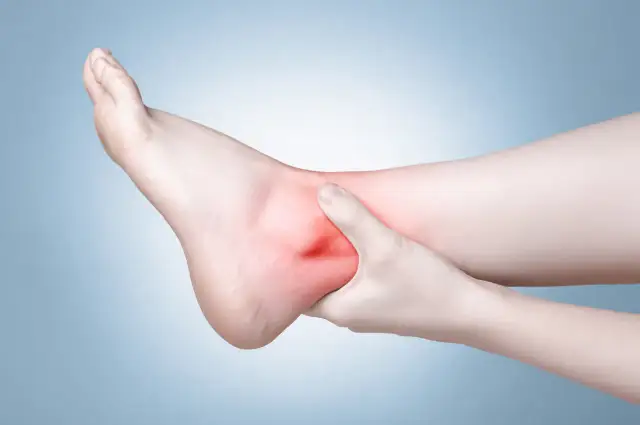

Ile trwa skręcenie kostki? Poznaj ramy leczenia dla stopni IIII, kluczowe czynniki rekonwalescencji i praktyczne porady, by bezpiecznie wrócić do aktywności.

Skuteczne metody, jak pozbyć się opuchlizny po skręceniu kostki. Dowiedz się, jak szybko wrócić do formy dzięki naturalnym sposobom i rehabilitacji.

Poznaj, jak długo boli noga po skręceniu oraz jakie są objawy i rehabilitacja. Dowiedz się, co wpływa na czas powrotu do zdrowia.

Dowiedz się, czym smarować skręconą kostkę, aby szybko złagodzić ból i obrzęk. Poznaj skuteczne maści i żele wspierające regenerację.

Zastanawiasz się, co jest gorsze: zwichnięcie czy skręcenie? Poznaj różnice, skutki oraz jak unikać powikłań zdrowotnych związanych z tymi urazami.

Znajdź odpowiednią maść na skręcenie kostki, która przyniesie ulgę w bólu i przyspieszy regenerację. Sprawdź skuteczne preparaty i ich działanie!

Skręcona kostka ile L4? Dowiedz się, ile dni zwolnienia lekarskiego przysługuje oraz jakie czynniki wpływają na czas rekonwalescencji.

Ile czasu goi się skręcenie stawu skokowego? Dowiedz się, jakie czynniki wpływają na czas regeneracji i jak skutecznie przyspieszyć powrót do zdrowia.